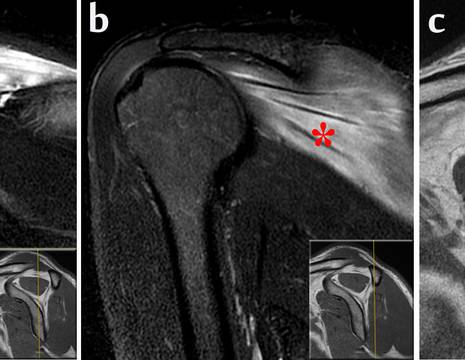

La risonanza magnetica (RMN) in questo è molto più precisa e può evidenziare anche precoci modificazioni strutturali muscolari conseguenti alla lesione del nervo. Inoltre può evidenziare la causa di compressione (cisti, massa solida) e può escludere altre patologie a sintomatologia analoga (rottura della cuffia rotatori, patologie del rachide cervicale…).

L’aspetto tipico RMN di un paziente con lesione del nervo sovra scapolare, è con edema muscolare di sovra e sottospinoso, con anche ipotrofia ed infiltrazione adiposa muscolare che compaiono però più tardivamente.